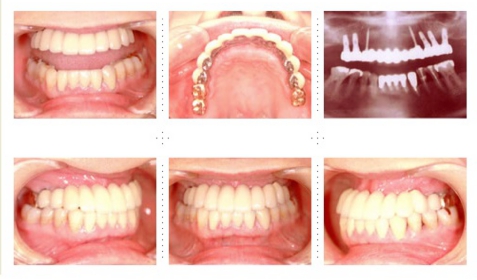

症例11

57才 女性

5年前に上顎に5本インプラントを埋入し、金属の冠をセットしました。インプラント部は快適に使用していたのですが、上顎の他の部位と下顎臼歯部のインプラントの治療を希望し来院。インプラント患者さんのリピーターが増加しております。

下顎は6本のインプラント埋入し冠をセット。上顎残存歯は将来を考え全て抜歯。4本のインプラントを追加埋入し、全顎ブリッジをセット。この様なケースが増えています。

以前のインプラントはそのまま使用可能で冠だけをやり直す事になります。